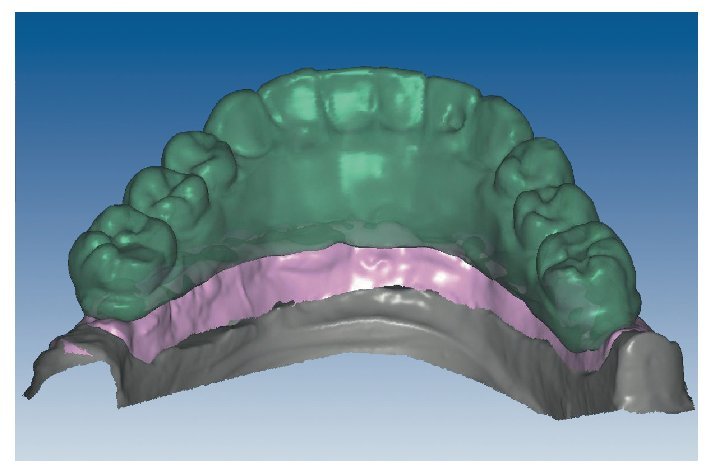

Mediante el uso de un escáner óptico de luz estructurada, los protocolos CAD registran los primeros datos relativos al modelo maestro con las correspondientes posiciones de implante (figs. 87 y 92). En el siguiente paso tiene lugar la digitalización de la planificación, previamente realizada en cera de escaneo matificada, de la restauración definitiva (figs. 88, 90 y 93). La subsiguiente conciliación de los datos mediante el uso del software de diseño dental permite al protésico planificar virtualmente el resto del procedimiento (figs. 89 y 91, 94 a 96) a partir del diseño de las estructuras (figs. 97 y 98).

Fig. 89. Planificación CAD de la estructura del maxilar superior.

Fig. 91. El diseño definitivo de la estructura para el maxilar superior.

Figs. 96 a 98. El diseño definitivo de la estructura del maxilar inferior, desde distintas perspectivas.